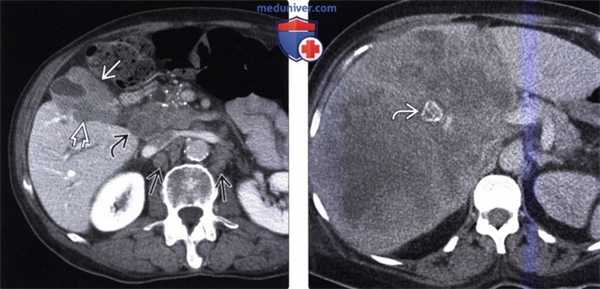

(Слева) На аксиальной КТ с контрастным усилением определяется рак желчного пузыря с инвазией в печень и нисходящую часть двенадцатиперстной кишки. Такие опухоли, если признаются резектабельными, однозначно требуют выполнения расширенной холецистэктомии и радикальной резекции.

(Справа) На аксиальной КТ с контрастным усилением визуализируется объемное образование в ямке желчного пузыря, прорастающее в печень. Во многих случаях, в том числе и в этом, место происхождения опухоли сложно определить.

(Слева) На аксиальной КТ с контрастным усилением определяется распространенное круговое утолщение стенки желчного пузыря, которое проспективно было расценено как проявление ксантогранулематозного холецистита. Тем не менее, во время оперативного вмешательства обнаружился рак желчного пузыря.

(Справа) На сонограмме визуализируется объемное образование в ямке желчного пузыря и конкрементдающий акустическую тень. Образование не отделено от прилежащих отделов печени. На КТ (томограммы не продемонстрированы) была обнаружена локальная инвазия рака желчного пузыря в центральные отделы печени.

(Слева) На аксиальной КТ с контрастным усилением определяется выраженное неравномерное утолщение стенки желчного пузыря, непосредственная инвазия печени, а также перипанкреатическая/портокавальная и забрюшинная лимфаденопатия. Увеличение лимфатических узлов этих групп является типичным проявлением рака желчного пузыря.

(Справа) На аксиальной КТ с контрастным усилением визуализируется большое гиподенсное образование в печени. Это образование может быть опухолью печени, однако желчный камень в его центре и невозможность визуализации желчного пузыря позволяют предположить, что образование представляет собой рак желчного пузыря с инвазией печени.